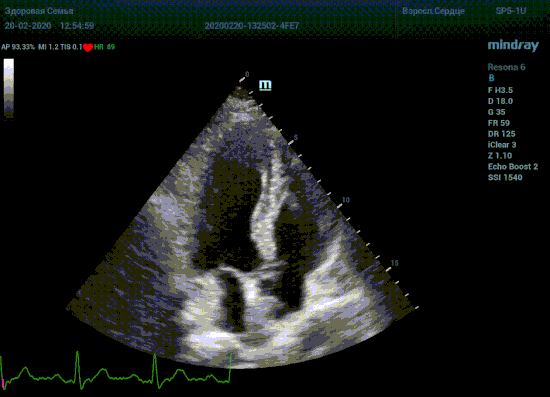

Детская кардиохирургия не исключение. Наиболее актуальная проблема — это дефекты межпредсердной и межжелудочковой перегородок, а также открытый артериальный проток. Не верная оценка гемодинамической значимости приведет к перегрузке правых отделов сердца и ряду осложнений, в случае если не прооперировать вовремя. Отправлять маленького ребенка под нож или подождать пока дефект перегородки зарастет сам? Ждем осложнений или ждать безопасно? На эти вопросы ответит Qp/Qs соотношение, рассчитанное методом эхокардиографии. Для этого необходимо рассчитать ударные объемы выносящих трактов желудочков, опять же на середине систолы – середине Т–зубца ЭКГ.